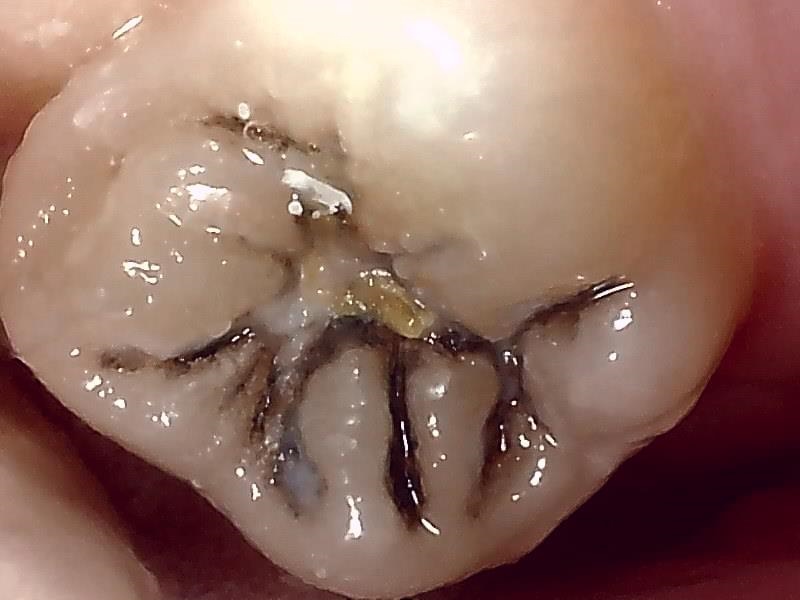

保険レジン充填の症例(奥歯)

Before

After

| 主訴 | 奥歯の虫歯を保険診療の範囲内で、かつ白く自然に治したい。 |

|---|---|

| 年齢・性別 | 30代 女性 |

| 治療方法 | コンポジットレジン充填 |

| 費用 | 保険診療 |

| 備考 | レジンはプラスチックを主成分とするため、金属(メタル)やセラミックに比べると強度が低いです。奥歯でグッと噛みしめる力が強い方や、歯ぎしりのある方は、稀に欠けたり割れたりすることがあります。 |